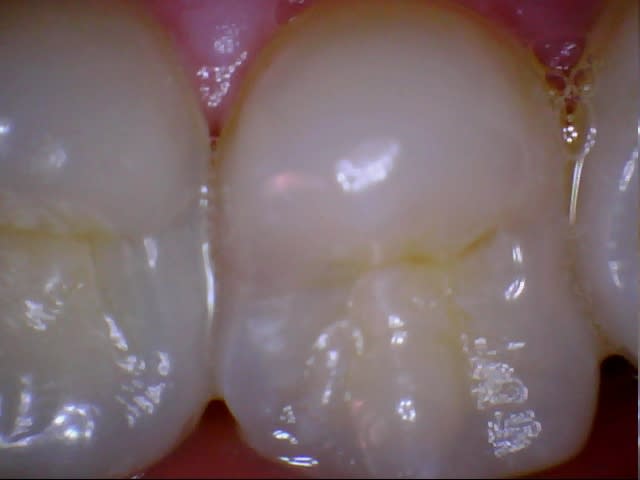

eMax de ce soir.

Collage automordançant G-Cem.